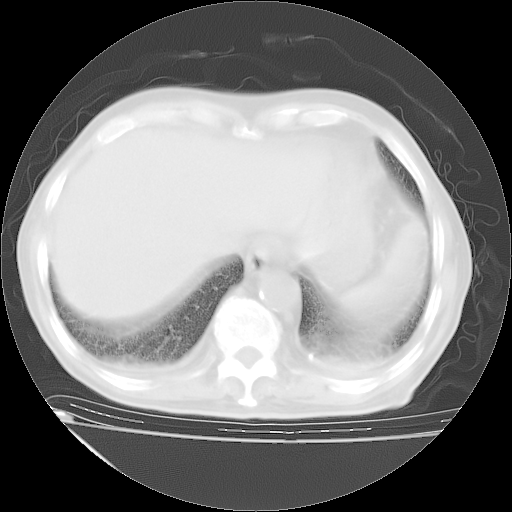

甲强龙80mg/日+抗结核治疗(异烟肼+利福霉素+乙胺丁醇)10天。复查肺部CT。

治疗10天肺部CT

补充下:5月9日胸部CT:似乎已见双下肺胸腔积液了,鉴于目前有下肢水肿,肝功示:白蛋白低,应注意多浆膜腔积液(漏出液可能大?),需注意!